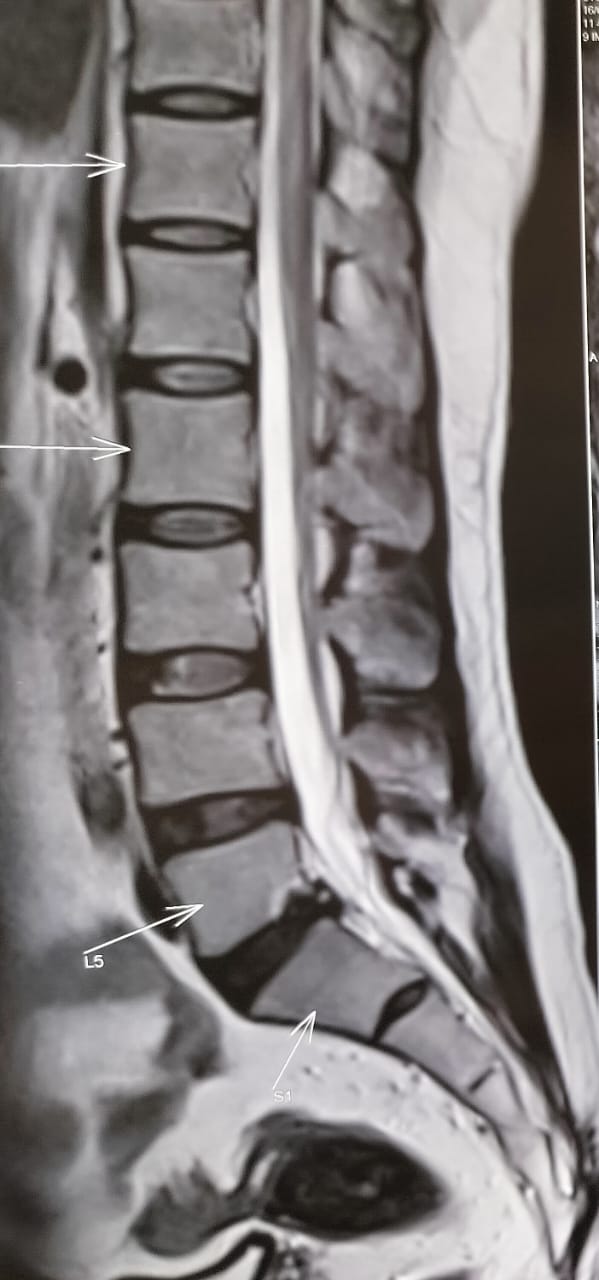

As this is favoring more of a lumbar canal stenosis we are getting his Lumbo sacral MRI inspite of the vascular priors gleaned by the previous evaluators elsewhere.

PPM 1 - This is his current MRI done in view of a clinical diagnosis of neurogenic claudication contrary to the angiography that was done elsewhere with a clinical impression of vasculopathy that was perhaps coincidentally vindicated on testing.